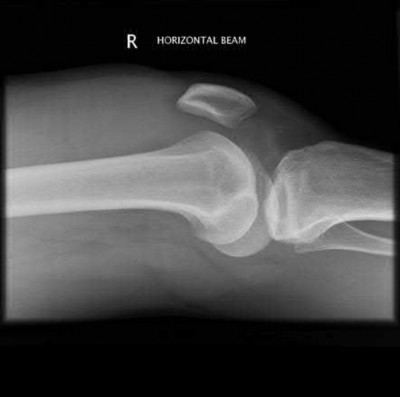

A 35-year-old male is involved in a high-speed motor vehicle collision and sustains the pelvic ring injury shown below.

In an Anteroposterior Compression Type III (APC-III) injury, which ligamentous complex is completely disrupted resulting in global pelvic instability?